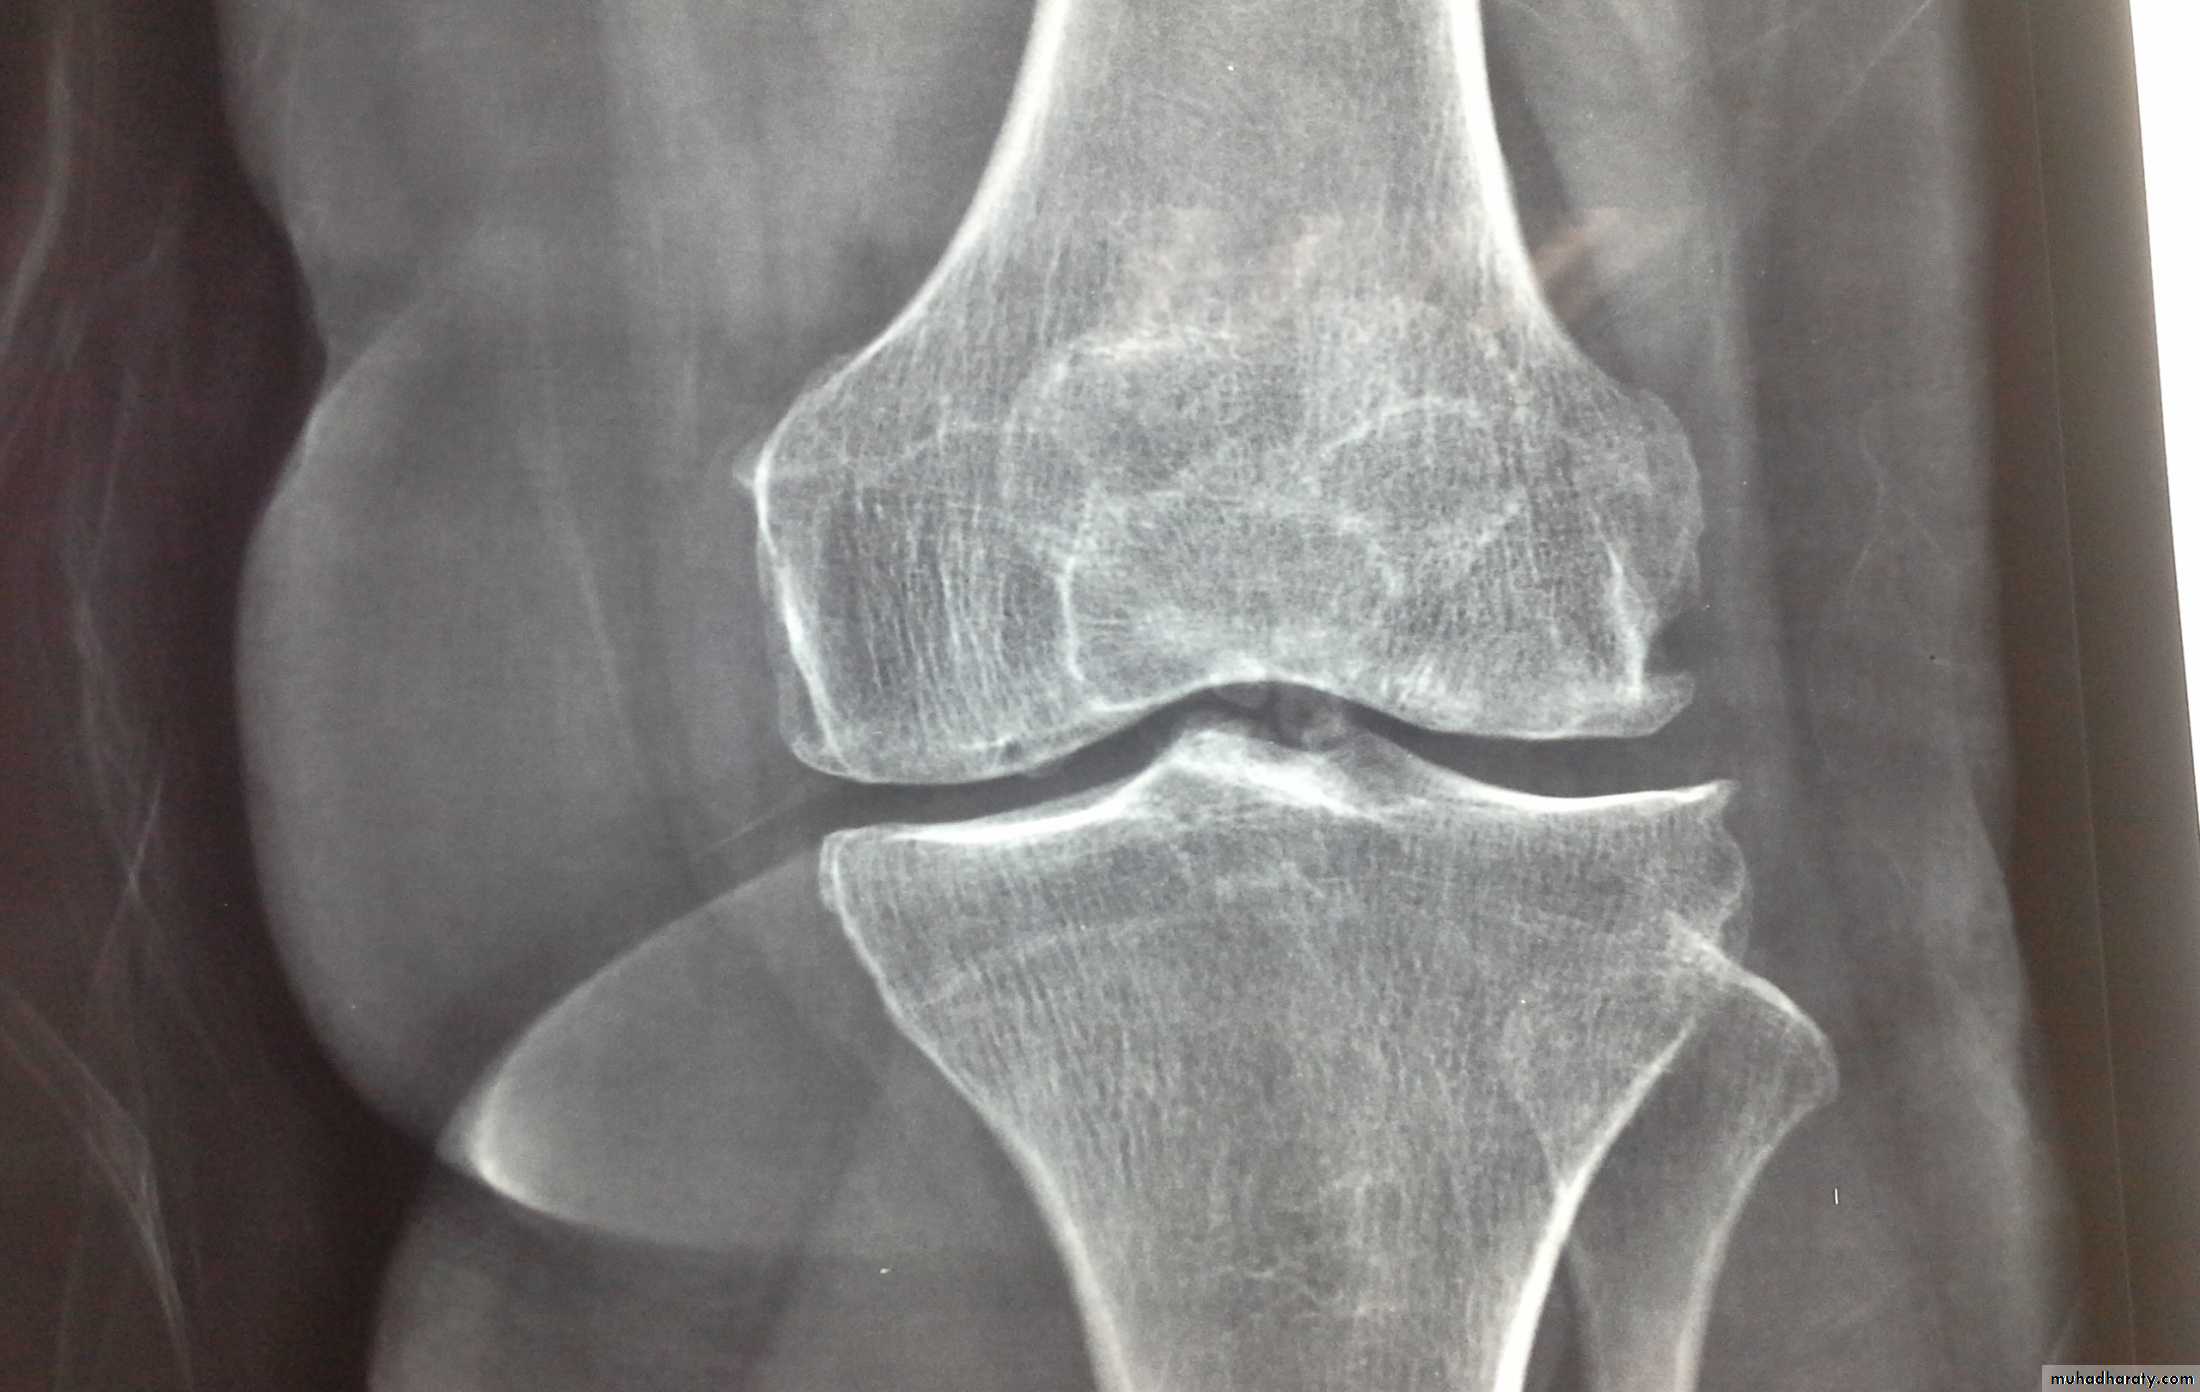

Dx of gout is established by Monosodium urate crystals viewed under the polarizing microscope. X-ray demonstrating typical gouty erosions at the first MTP joint, with well-demarcated erosions, away from the joint line, some with overhanging edges, and adjacent hazy tophaceous material.

-Radiograghs which is :

a-Normal in early stage

b-Later :joint space narrowing ,sclerosis,cyst, osteophyte and gouty erosions( para articular punched out defects)